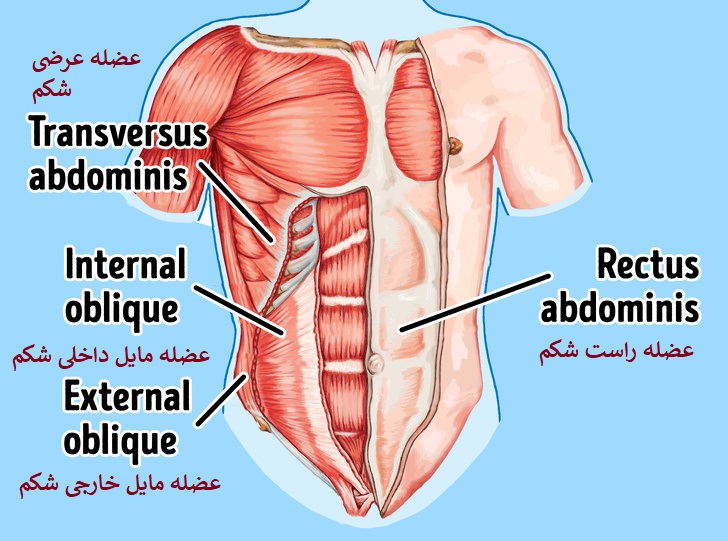

عکس داخل شکم انسان. در این همان طور که مشخص است شکم حالت بیضی شکل پیداکرده و این بیضی که کناره های شکم کشیده شده است. تعداد سلول های بدن انسان حدود ۳۷ ۲ تریلیون تخمین زده شده اند. Abdomen که در زبان عامه به غلط به آن دل نیز می گویند در آناتومی به قسمتی از تنه گفته می شود که مابین دیافراگم از بالا و سطح فوقانی لگن خاصره از پایین قرار دارد. ربات دیدنی ربات انساننمای چینی به صورت یک دختر جوان ساخته شده و جیا جیا نامگذاری شده است این ربات طوری برنامهریزی شده که میتواند صحبت کند و احساسات خود را از طریق تغییرات در چهره حالات.